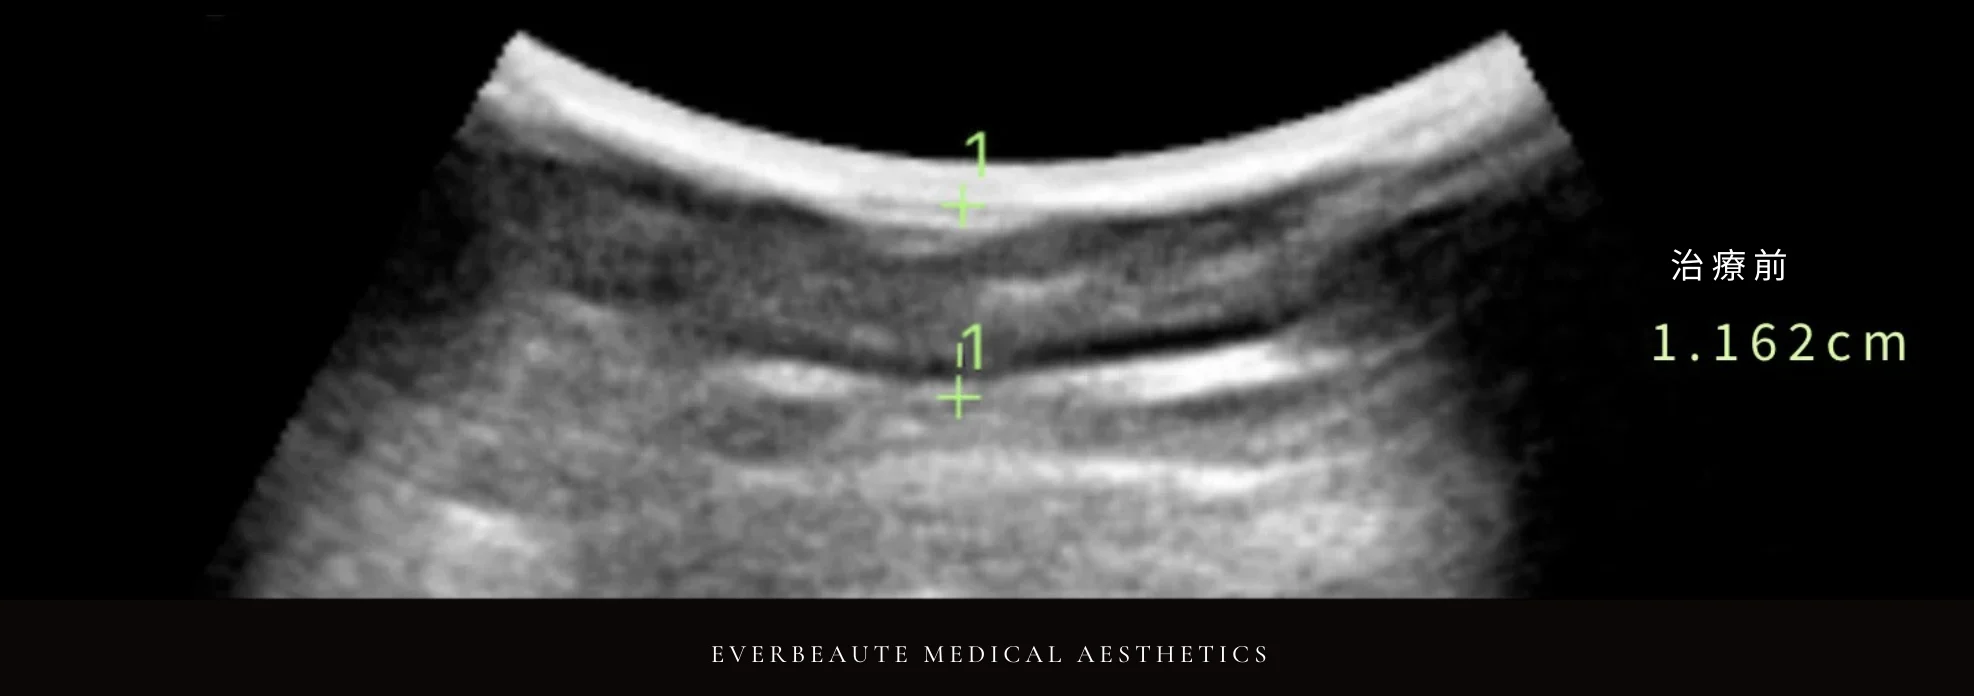

經術前與術後超音波檢查比較,上臂脂肪厚度由1.162公分減少至0.852公分,顯示脂肪厚度下降約26.7%,呈現顯著改善。